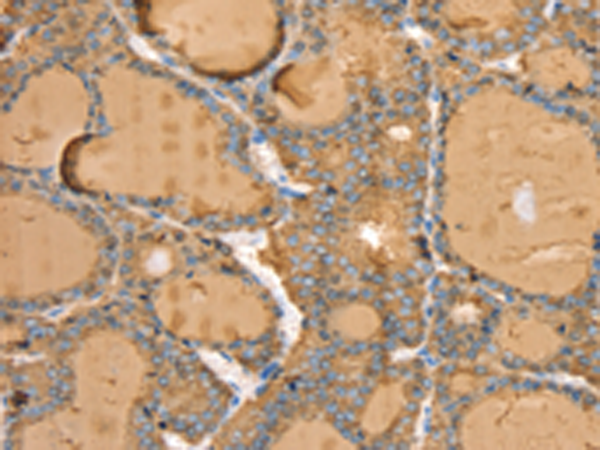

IHC positive control: |

Human thyroid cancer |